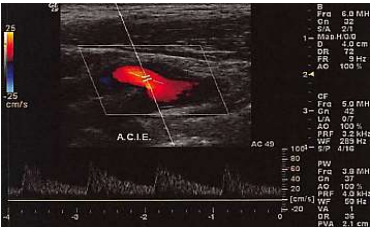

Assinale a alternativa que apresenta a melhor descrição do formato de onda mostrado na imagem abaixo.

Provas